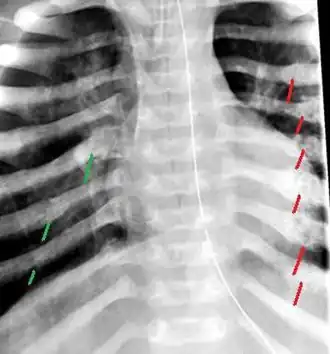

Ces lésions métaphysaires sont très spécifiques : notamment celles du fémur, humérus, tibia... mais aussi les fractures postérieures de côtes, fracture de l’omoplate, fracture d’une épineuse vertébrale[8].

Au total, le type et la localisation des fractures peuvent orienter vers le type de traumatisme : choc direct (fracture du crâne, fracture diaphysaire...), traction ou torsion (fracture métaphysaire), bébé fortement secoué ou serré (hématome sous-dural, fractures de côtes...)[6].